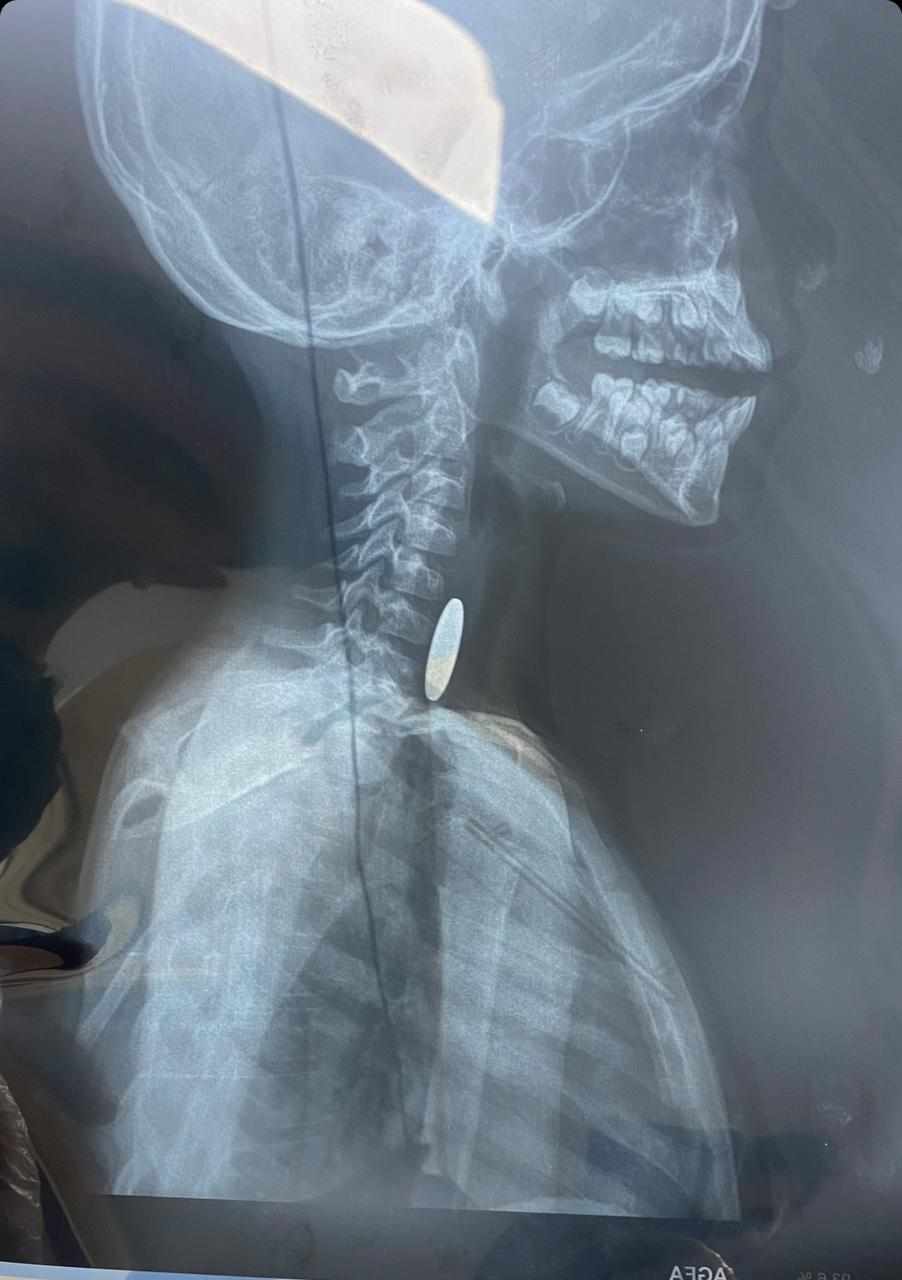

وقال رئيس الطاقم والمشرف على الحالة ، إختصاصي دقيق جراحة الجهاز الهضمي والكبد ، الدكتور أحمد هاشم ، إنه "تم إستقبال الطفل مُحالاً من قسم طوارئ المدينة الطبية ، عصر أمس الجمعة ، وهو يشكو إبتلاع جسم غريب ( قطعة نقود معدنية) كانت قد عُلِقّت في منطقة البلعوم ( تبيّن من خلال الفحص بالأشعة ) ، مما تسّبب في إختناق وعدم القدرة على البلع ، حيث قرر الطاقم الطبي إجراء عملية عاجلة بالمنظار لإزالة الجسم الغريب

، وقد كُللت العملية بالنجاح دون حدوث مُضاعفات "، مُشيراً الى ان "الطفل ، وضع تحت المراقبة لحين تماثله للشفاء تدريجياً ، ومن ثم مُغادرته المركز بصحبة ذويه وهو بصحة جيدة ".